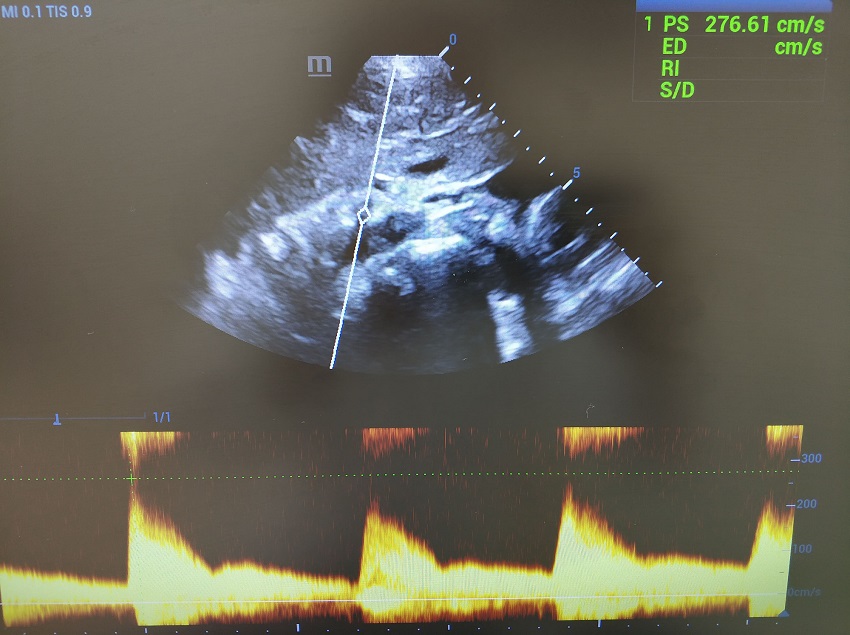

Цветовая карта color бокса, сопряженно со вдохом и выдохом, как по нажатию выключателя показывала и скрывала факел элайзинга. Какая же там скорость? Кнопка PW (Pulsewave, или импульсно-волновой допплер) издала щелчок. Линия стиринга, по всем законам физики и технике исследования расположилась строго по ходу сосуда, никакой угол коррекции при исследовании ветвей аорты не допускается. Контрольный объем погрузился в точку истока чревного ствола и медленно начал движение от аорты в ствол. Прибор зашумел в такт пульсации артерии, озвучивая спектр потока. PSV 98 см/сек… 100 см/сек… 150 см/сек..., похоже максимум.

Повторяем маневр, контрольный объем скользит в чревный ствол. Прибор переходит на визг,  ручка Scale вправо - увеличиваем шкалу и пульсация затихает. Калипер поднимается на вершину систолического пика, PSV  276  см/сек. Максимум ли? Переходим в режим постоянно волнового CW-допплера, фокус в зону истока чревного ствола. Да, максимум.